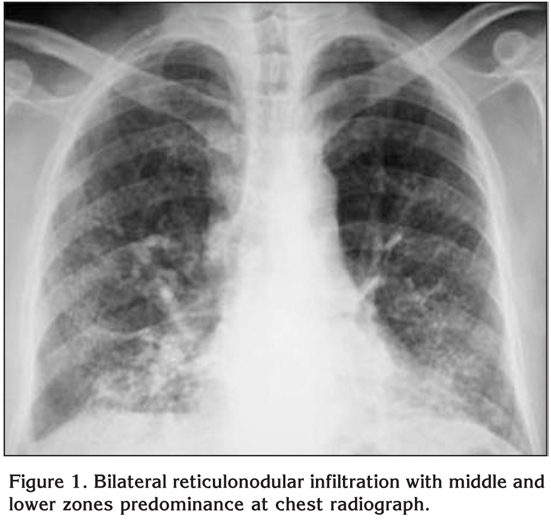

On physical examination oculocutaneous albinism, strabismus, nystagmus, clubbing and bilateral inspiratory rales were detected. The temperature was normal, the blood pressure 100/60 mmHg, the pulse 112 beats per minute and the respiratory rate 28 breaths per minute. Laboratory studies revealed a normal complete blood count and serum biochemistry. The prothrombin time, partial-thromboplastin time and international normalized ratio were in normal range, however, the bleeding time was prolonged (14 minutes; normal: 2-9 minutes). Chest radiograph showed bilateral reticulonodular infiltration with middle and lower zones predominance (Figure 1). A thorax computed tomography (CT) revealed bilateral diffuse interlobular septal thickness and traction bronchiectasis which were more prominent in the basal segments of lower lobes and also a honeycomb pattern (Figure 2). The oxygen saturation was 66% while the patient was breathing ambient air and arterial blood gas analyses revealed severe hypoxemia with a PaO2 value of 36.7 mmHg. Accordingly, oxygen therapy was initiated. Since supplemental oxygen by nasal cannula failed to increase the oxygen saturation above 90%, oxygen was given by a face mask with reservoir bag. During follow-up, although pirfenidone therapy was planned, clinical deteroriation developed and the patient died at the 14th day of hospitalization because of the respiratory failure.

Figure 2

The radiologic appearance of pulmonary fibrosis in HPS is comparable to that of idiopathic pulmonary fibrosis and the predominant radiologic pattern is interstitial patterns or infiltrates that usually involve both lungs symmetrically as in our case.